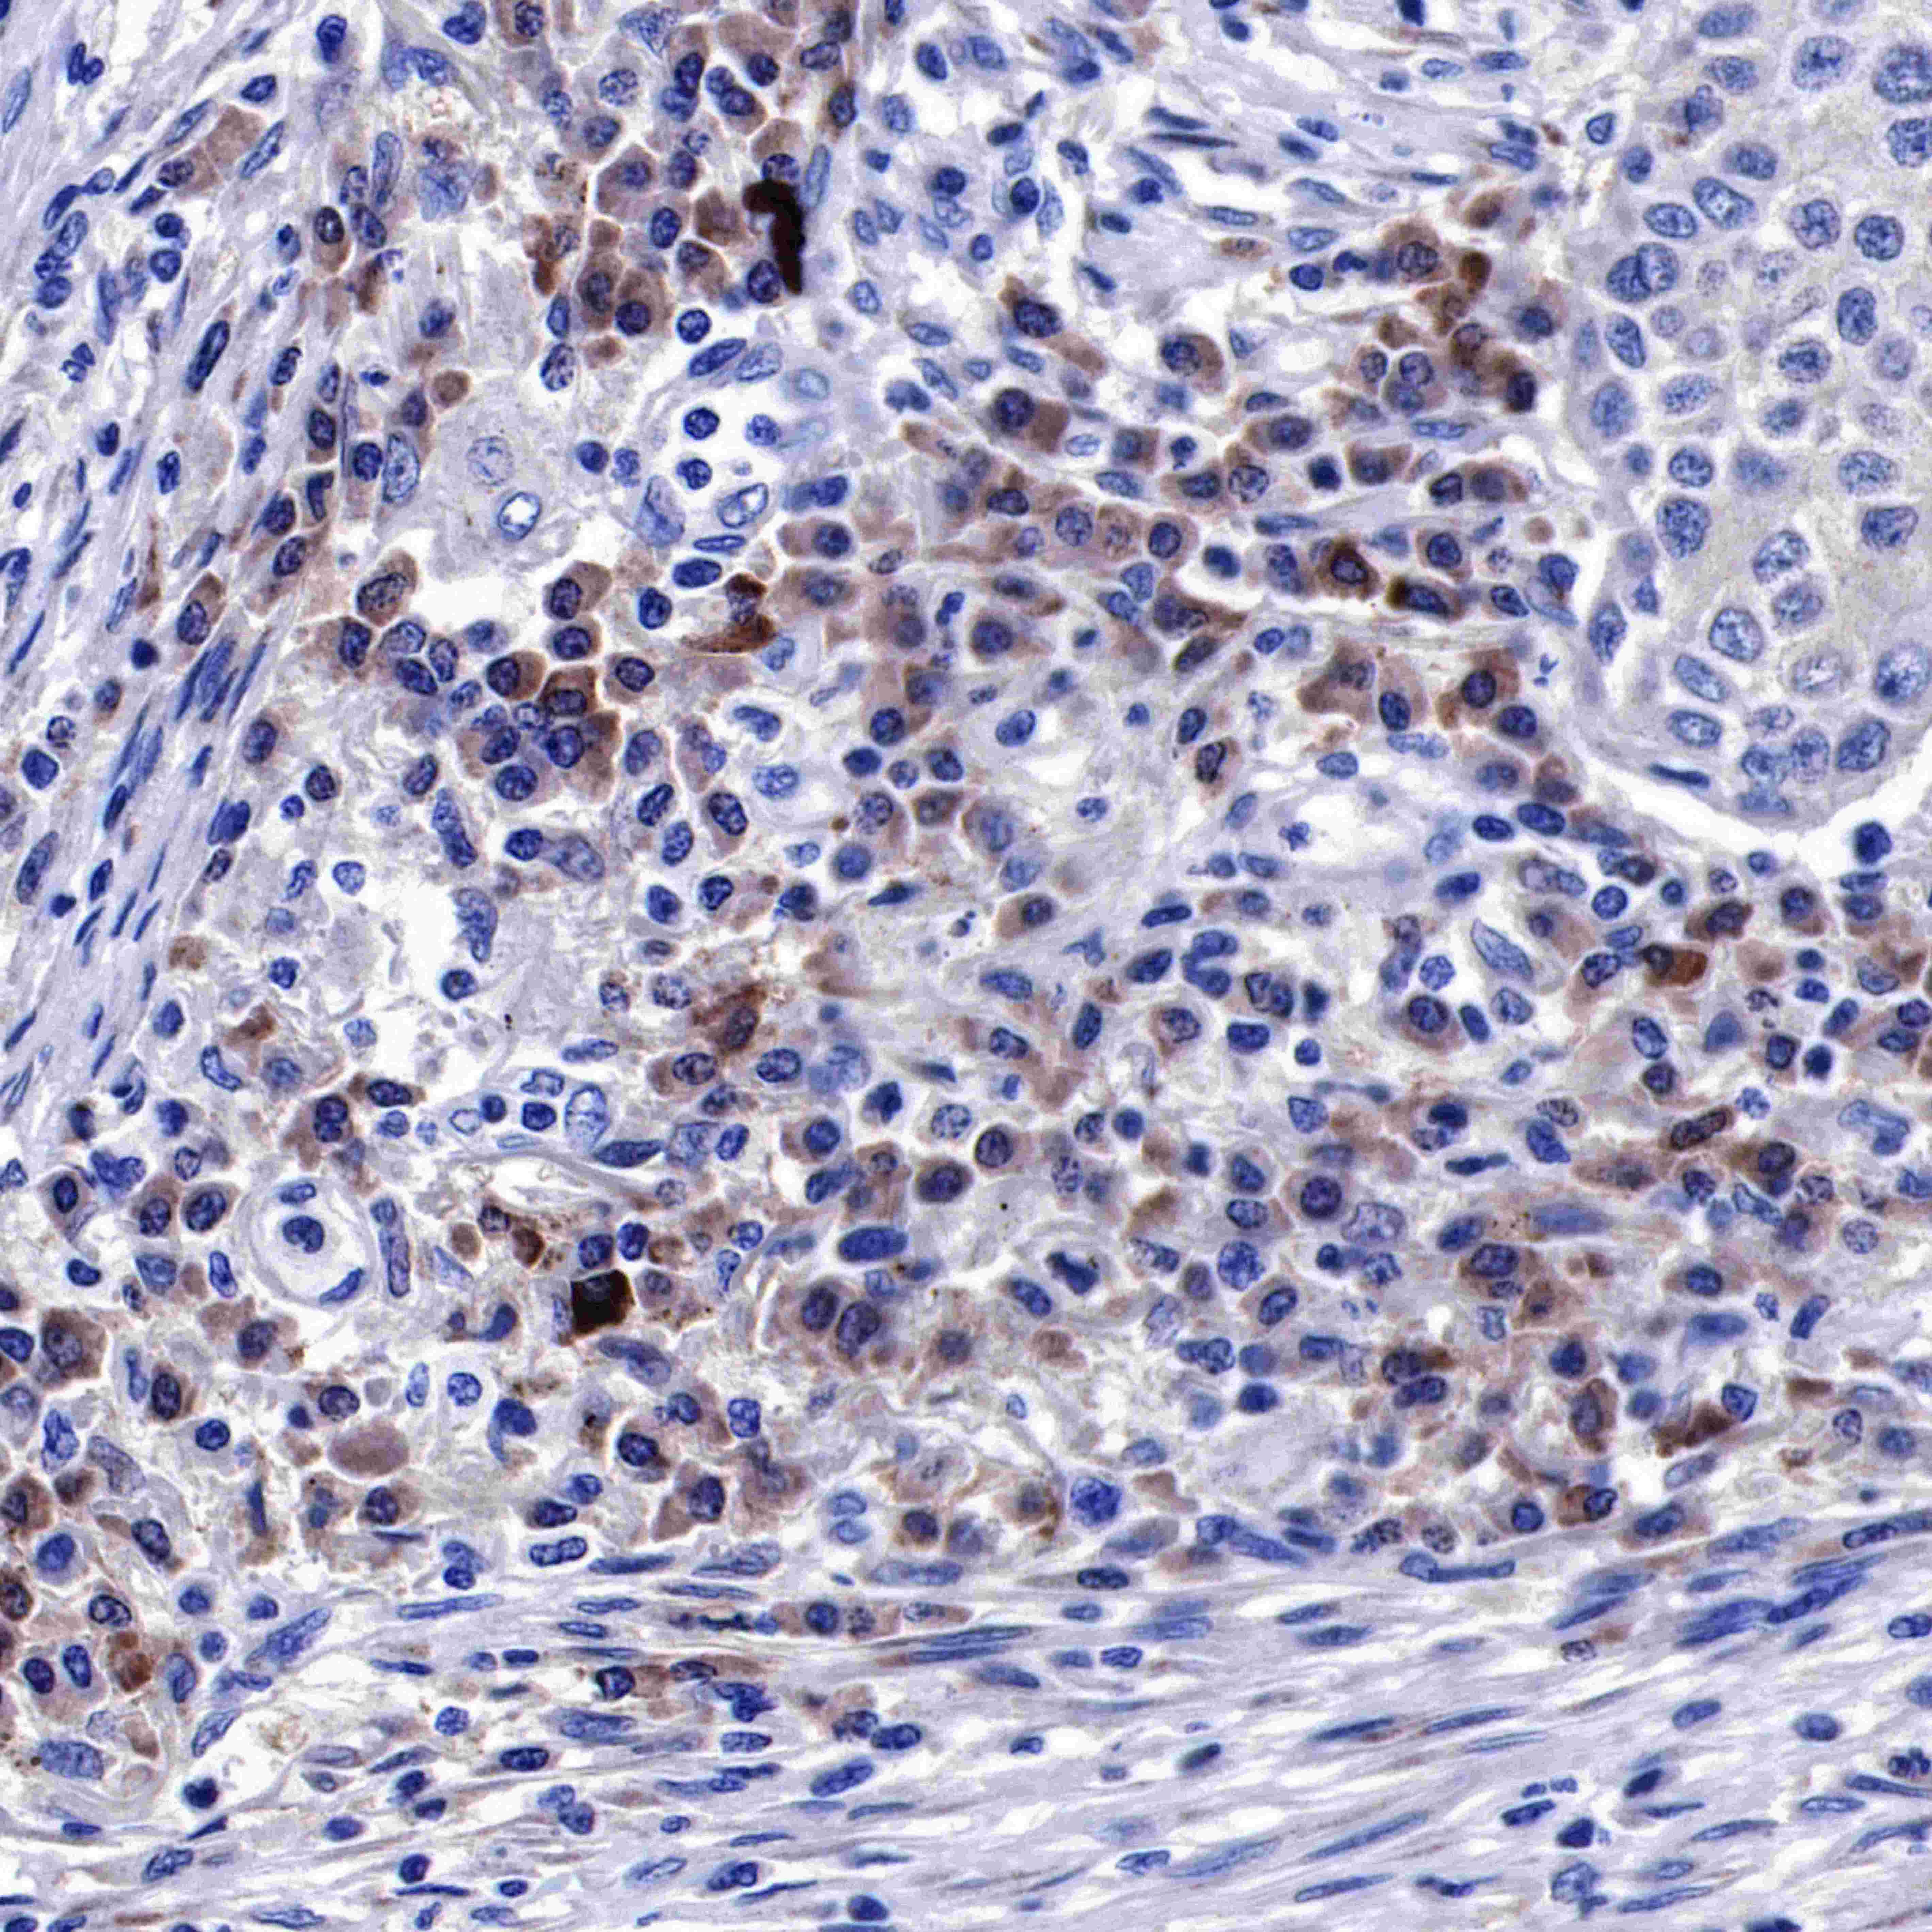

Immunohistochemistry

GST-π is abundantly expressed in some mammalian tissues, particularly those associated with malignancies. While the enzyme can catalyze thioether bond formation between some electrophilic chemicals and GSH, novel non-detoxification functions are now ascribed to it.